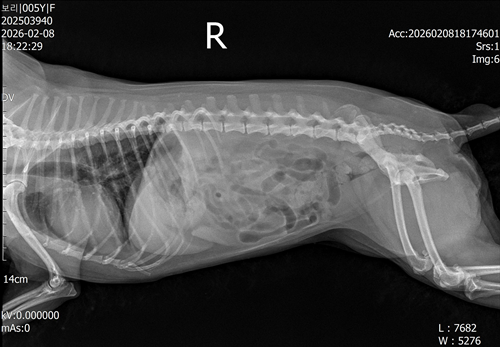

강아지 슬개골탈구 진단 받았습니다 몇군데 병원을 다녀봤는데 진단이 달라 궁금해서 질문 해봅니다 일단 저희 강아지는 오른쪽 다리를 갑자기 들고 다니고 절어 병원을 방문하게 되었고요 왼쪽은 증상이 없지만 오른쪽만 있는 상태였습니다 첫번째랑 두번째 병원에서는 슬개골 탈구 진행중이고 왼쪽이 3기 오른쪽이 2기 정도라고 했습니다 하지만 왼쪽은 아예 빠져있어 증상도 없고 아파하지도 않는다고 했고 오른쪽은 빠졌다 안빠졌다 해서 증상이 있다고 했고 십자인대가 파열된 걸론 보이지 않는다고 했습니다 그래서 양쪽 슬개골탈구 수술만 진행하면 된다고 했고요 근데 세번째 병원에서는 둘다 왼쪽이 좀 더 심한 슬개골 탈구 3기 정도라고 했고 오른쪽만 십자인대 부분파열이 보인다고 했습니다 그래서 십자인대 파열이 아닌 왼쪽은 굳이 수술할 필요가 없고 나중에 십자인대 파열이 오거나 증상이 나타나면 그때 수술하면 된다고 했습니다 그래서 오른쪽 슬개골탈구 수술과 tplo를 하는 방식으로 수술을 한다고 했습니다 여기서 궁금한점은

3. 꼭 슬개골탈구와 십자인대 수술을 같이 해야 결과과 더 좋아지나요?

4. 사진상으로 십자인대와 슬개골 수술을 같이 해야할까요? 5. tplo 수술방법이 가장 안전하고 좋은 수술방법인가요?

6. 슬개골탈구로 인해 십자인대가 끊어지는건 아니라고 들었는데 맞나요? 슬개골 탈구 수술로 십자인대를 예방할 수 있나요?